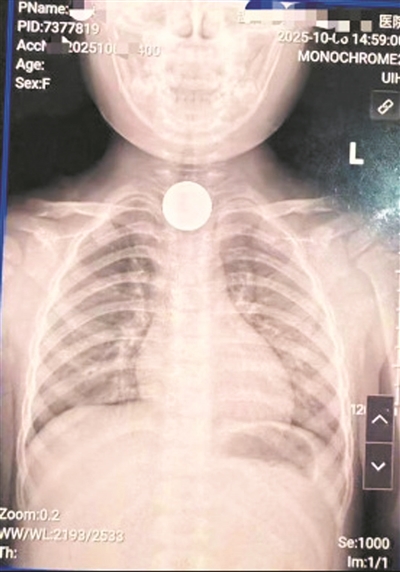

好险!女孩误吞硬币被“锁喉” 医生用导尿管巧取

温州网讯 近日,一名4岁女孩在玩耍时不小心吞进一枚硬币,卡在了细小的食管里,随时都有可能引发窒息、黏膜损伤等严重并发症。一场争分夺秒的抢救在温州市人民医院、温州市妇幼保健院急诊科展开。

当天,正在休假的该院消化内科副主任医师翁雪健在接到医院的电话后,马上从家里出发赶到医院。此时,女孩因为喉咙被异物卡住导致不适和惊吓啼哭不止,翁雪健立即进行检查评估,决定采用创伤极小的无菌导尿管去取女孩喉咙中的异物。

在助手的配合下,翁雪健精准快速地将无菌导尿管放置在女孩的食道,巧妙地绕开硬币并建立了在食管内的支撑,轻柔地把卡在食管处的硬币“带”了出来,全程仅用时5分钟。在场的女孩家长悬着的心终于放了下来,连忙道谢。

医生用一根导尿管巧取,仅用时五分钟化险为夷